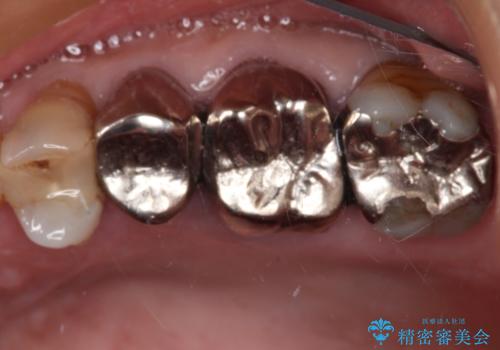

- 詰め物が欠けてしまい、虫歯かもしれないから診てほしいとのことで来院された患者様です。

精査の結果、詰め物の下に虫歯が大きく広がっているのがわかりました。

虫歯の範囲が大きく、部分的な詰め物では対応が難しいため、オールセラミッククラウンにて補綴することとしました。